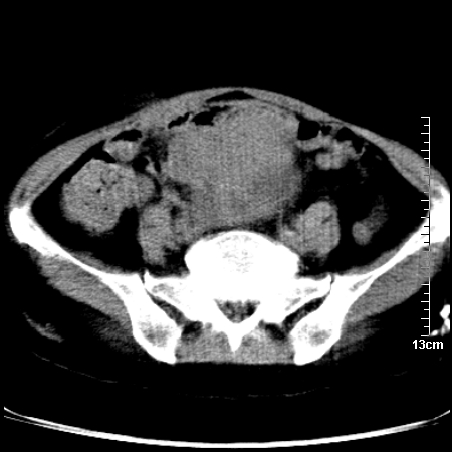

术前的疏忽,手术前诊断阑尾炎,但是没有常规做b超,导致术后1周检查发现 1。实性包块?2。腹腔术后脓肿?

病史:病人一周前诊断阑尾炎,未做b超,手术发现阑尾化脓,(没有留意有无包块),术后1周病人发热,血象:1.6万,做b超发现,随ct检查,上传图片

巨大囊实性包块,边界大部尚清楚,不太像脓肿的表现。应该做个增强检查除外盆腔肿瘤。

脓肿可能性大. 因回盲部区域化脓性兰尾切除残端感染改变征像与实性肿块关系密切.肿块上界至右下腹,下界至盆腔膀胱上缘, 如果是实性肿块在兰尾术中可能就会发现. 所以术后一周病人高烧, 白细胞增高,临床表现支持脓肿.

盆腔一边界大部份清晰囊实性肿块,其周腹脂未见确切异常,其一端与右侧附件相连。考虑右侧附件肿瘤。

如果能进行肠道准备就好了!盆腔内巨大囊实性包块,右前缘与周围肠管分界不清,病灶内前部的气体是否为肠管内气体形成的假象不能确定。

这么大一包快手术当中没有发现?值得怀疑!结合化脓性阑尾炎病史,首先考虑脓肿!不排外附件来源的肿瘤,建议增强扫描!!

因术前未做相关检查,故漏诊完全有可能!若脓肿这么大,临床不会单纯是阑尾炎的体征!支持:盆腔肿瘤——首选:附件来源的肿瘤,建议增强扫描!!!